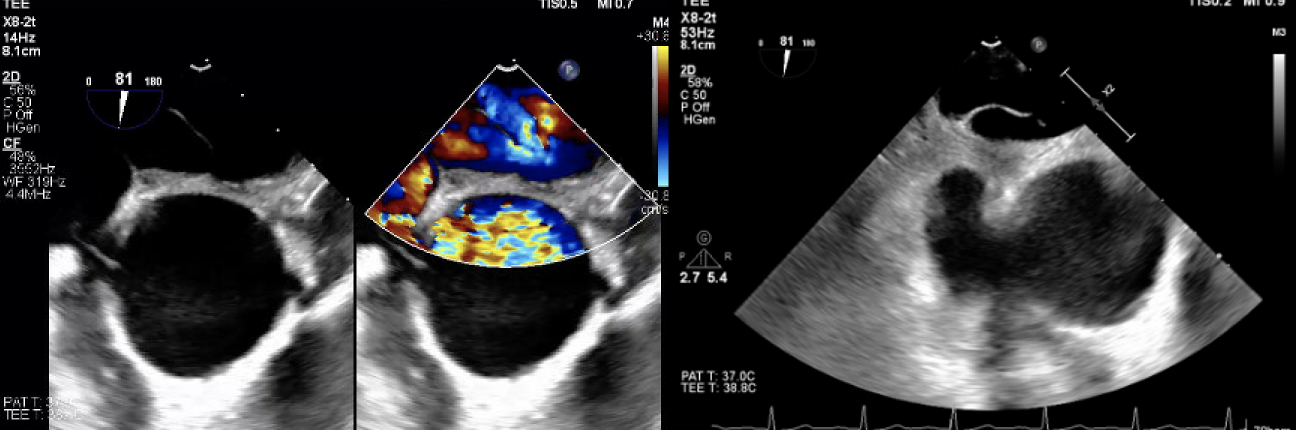

A 78-year-old man with a history of Parkinson’s, TIAs, and scoliosis presented with a sequalae of symptoms concerning for recurrent TIA, however extensive workup demonstrated no evidence of acute intracranial abnormalities. Subsequently, he developed acute hypoxic respiratory failure requiring high-flow nasal cannula. Initial chest CT angiography (CTA) and X-ray were negative for acute pulmonary pathology. A transthoracic echocardiogram (TTE) with bubble study was positive for moderate right-to-left shunt through a patent foramen ovale (PFO). Subsequent imaging modalities, including right heart catheterization, transesophageal echocardiography (TEE) with bubble study, cardiac CT, and cardiac MRI, exhibited normal hemodynamics, positive PFO with left-to-right shunt, and no evidence of significant right-to-left shunt (normal Qp:Qs). Of note, he was discovered to have significant hypoxia while sitting up but remained on room air while supine. In order to evaluate for platypnea-orthodeoxia syndrome (POS), TTE with agitated saline contrast was performed which was grossly positive after 5 cardiac cycles while in the supine position and 3 cardiac cycles while upright, raising concern for pulmonary arteriovenous malformations (AVMs). However, repeat CTA was negative for pulmonary AVMs. Finally, repeat TEE bubble study was performed while the patient was supine (Images A) and sitting up (Images B) which demonstrated a PFO with bidirectional shunting. While the patient was sitting up (Images B), there was stretching of the PFO with significant, continuous right-to-left shunting likely precipitated by the patient’s significant scoliosis. The patient underwent successful percutaneous PFO closure (Images C), which immediately resolved his hypoxia.